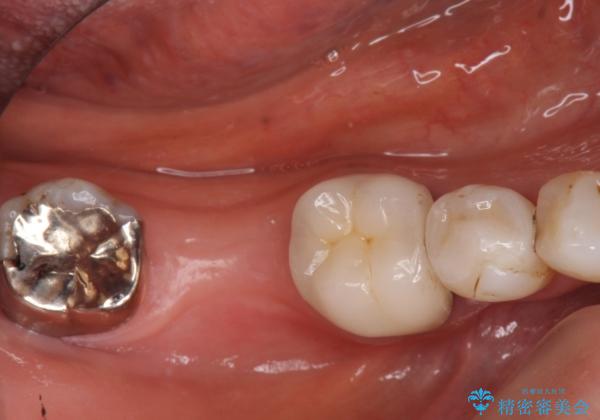

- 68.2万円 内訳(ストローマンインプラント22万円、カスタムアバットメント11万円、ジルコニアクラウン11万円、マイナーGBR5.5万円、FGG(遊離歯肉移植)11万円、静脈内鎮静5.5万円、矯正用仮歯2.2万円)(旧料金)費用は治療当時の料金となります

他院で抜歯後いらしたため、骨ができるのを待って、オペは2回法で行っております。

2回法の利点は、骨増成が確実であることと、FGGが可能で長期に安定した歯ぐきが得られることです。